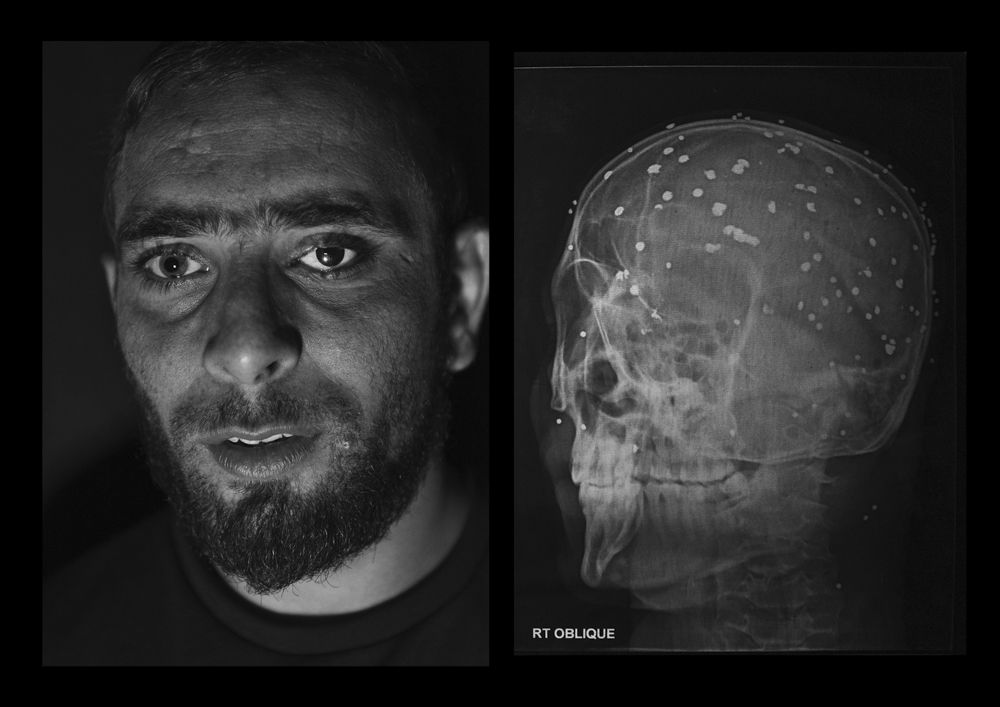

The valley of Kashmir, disputed by India and Pakistan since 1947, is one of the most militarized zones in the world.

In the last years, the Indian government provided the security forces deployed with a new weapon: a shotgun that fires hundreds of metal pellets to keep the urban protests under control. Defined as “non-lethal”, according to a UN report released in 2018, the weapon is responsible for blinding around 1000 people.

Left partially or totally blind, victims speak of the darkness descended upon their lives. The only things left to see are the faint shadows that surround them.